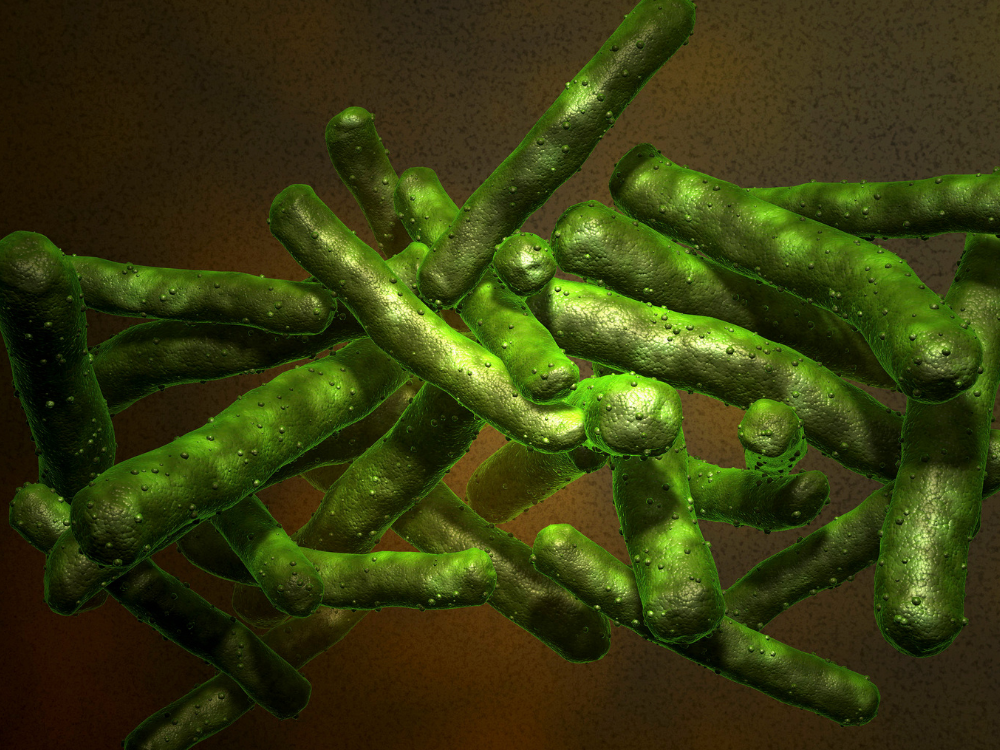

Bệnh lao, hay còn gọi là Tuberculosis, là một bệnh truyền nhiễm chủ yếu qua đường hô hấp, do vi khuẩn Mycobacterium tuberculosis gây ra. Bệnh không chỉ tấn công phổi mà còn có thể ảnh hưởng đến các bộ phận khác của cơ thể như xương, não và thận. Bài viết này sẽ tập trung chủ yếu đề cập đến lao phổi.

Bệnh lao do vi khuẩn Mycobacterium tuberculosis (vi khuẩn lao) gây ra.

Mycobacterium Tuberculosis trong điều kiện tự nhiên có thể tồn tại từ 3 – 4 tháng, là một vi khuẩn ái khí vì vậy ưa cư trú trong môi trường có nhiều oxy do đó thường khu trú ở phổi và số lượng vi khuẩn có nhiều nhất trong các hang lao có phế quản thông.